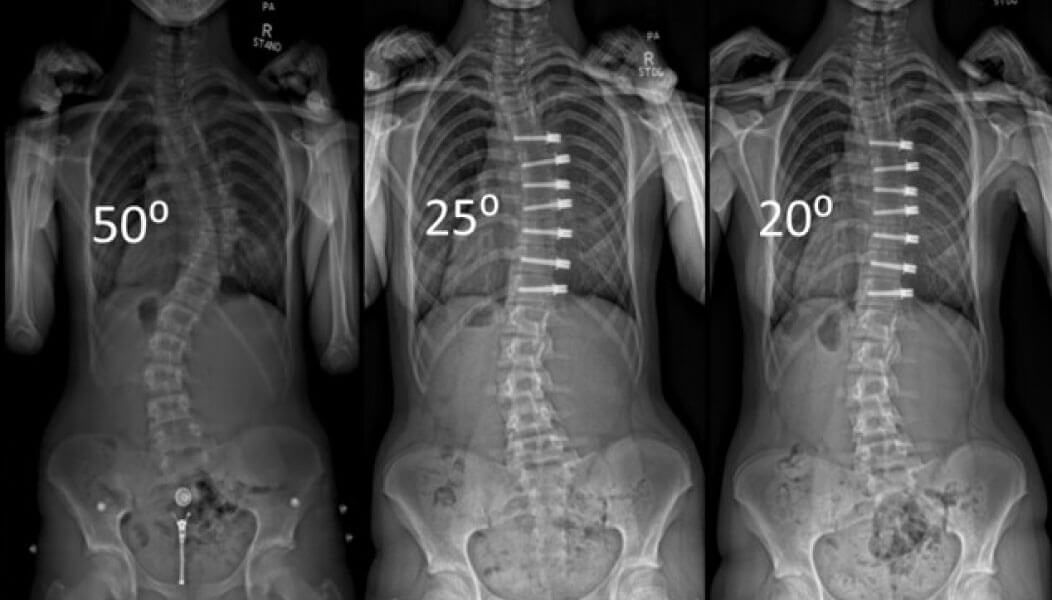

Cuando llegó a Mayo Clinic en el 2011, la Dra. Larson se encontró con que solo había una opción para la escoliosis grave: la cirugía de fusión espinal. "Había dispositivos temporales, como la varillas de crecimiento, que ayudaban a los niños durante la edad escolar. Pero una vez que tenían edad suficiente, se les practicaba una fusión espinal", describe. La fusión espinal consiste en fijar tornillos y varillas en la columna vertebral para sostenerla en una posición rígida más correcta. Un efecto secundario de la cirugía de fusión espinal es que los niños pueden perder significativamente la amplitud de movimiento. Además, la recuperación puede ser un proceso largo e incómodo.

"Cuando empecé a trabajar en este campo, me di cuenta de que lo que hacíamos en el 2012 era similar a lo que se hacía en 1975", relata. Sabía que era posible hacerlo mejor. Fue entonces cuando se enteró de un procedimiento prometedor conocido como anclaje de cuerpos vertebrales. En el 2015, la Dra. Larson visitó los pocos hospitales donde se practicaba el procedimiento y llevó la técnica a Mayo Clinic. "Hicimos nuestro primer procedimiento de anclaje vertebral en el 2015. En ese momento, era tan novedoso que la Administración de Alimentos y Medicamentos de Estados Unidos (FDA, por sus siglas en inglés) aún no lo había aprobado. Tomábamos tornillos y un cordón para fusionar la parte posterior de la columna vertebral y, realmente, los poníamos en la parte delantera de la columna".

En lugar de hacer una única incisión larga en la espalda, el anclaje del cuerpo vertebral consiste en hacer pequeñas incisiones en el costado y, en lugar de usar 20 tornillos y 2 varillas, el cirujano solo coloca en cada vértebra un tornillo conectado a un cordón flexible para enderezar la columna vertebral. Además, la columna vertebral no pierde flexibilidad porque, en lugar de varillas rígidas de metal, se usa un cordón plástico que se extiende a medida que el niño crece. De esta forma, el paciente tiene mucha más libertad de movimiento y se recupera más rápido. A medida que el niño crece, la columna vertebral puede enderezarse incluso más. La Dra. Larson agrega: "Es un procedimiento mucho menor que permite conservar la funcionalidad".